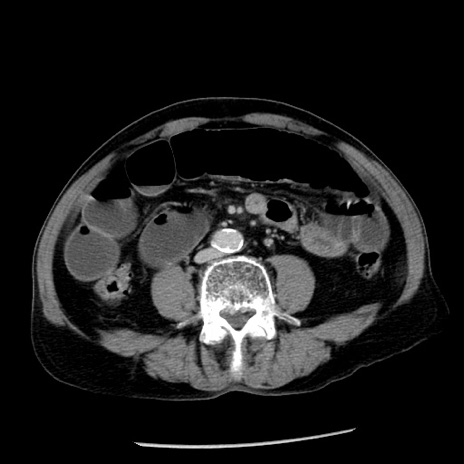

症例26(横断像)

【症例】80歳代男性

【主訴】嘔吐

【現病歴】昨晩2回嘔吐あり、今朝になっても嘔吐あり。来院。

【既往歴】胃潰瘍

【身体所見】意識清明、BT 37.6℃、BP 166/95mmHg、HR 100bpm、SpO2 97%、腹部:平坦・軟、腸蠕動音聴取良好、圧痛なし。

【データ】WBC 21900、CRP 1.46